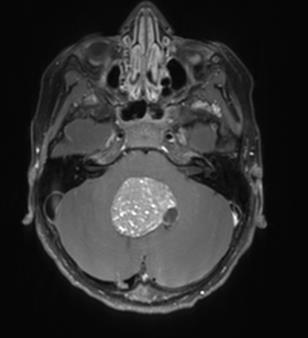

GLIOBLASTOM

Glioblastom er den vanligste formen for høygradig gliom og utgjør rundt 90 % av alle grad 4-gliomer hos voksne (Figur 1). Den aldersjusterte insidensen i Norge er 5,3 per 100 000 personår, med 251 nye tilfeller i 2024 (1). Median alder ved diagnose er 64 år, og sykdommen forekommer noe hyppigere hos menn. Standardbehandlingen har vært uendret siden 2005 og består av maksimal kirurgisk reseksjon, etterfulgt av konkomitant behandling med stråling og det alkylerende legemiddelet temozolomid, og deretter adjuvant temozolomid (5). For yngre pasienter som gjennomgår full behandling er median overlevelse 15 måneder med en toårs overlevelse på 27% (5). Norske populasjonsdata har bekreftet disse tallene, men viser at median overlevelse i en uselektert populasjon er rundt 12 måneder og toårs overlevelse 17% (6). Prognosen påvirkes av pasientens funksjonsstatus, alder, behandlingsintensitet og MGMT-metyleringsstatus, der sistnevnte indikerer respons på behandling med temozolomid (5,7). Siden introduksjonen av kjemoterapien temozolomid i 2005 er det ikke innført noen nye behandlingsmodaliteter. Likevel har overlevelsen gradvis bedret seg, der forbedringer i den kirurgiske behandlingen trolig har spilt en sentral rolle (6).

Kirurgi er den første og viktigste behandlingsmodaliteten ved glioblastom. Det sikrer vev for histopatologisk og molekylær diagnose, lindrer symptomer, reduserer tumorbyrden og bidrar til lengre overlevelse. Målet er maksimal trygg reseksjon – å fjerne mest mulig tumorvev uten å påføre pasienten varig nevrologisk skade. En rekke studier har vist en klar sammenheng mellom grad av reseksjon og overlevelse (8,9,10), noe som også er vist i norske populasjonsdata (6). Data fra det norske kvalitetsregisteret fra 2019-2023 viser at 85 % av pasientene gjennomgikk reseksjon som primærbehandling, mens 15 % gjennomgikk en diagnostisk biopsi (11). Den postoperative 30-dagers mortaliteten var 1,5 % etter reseksjon (12).